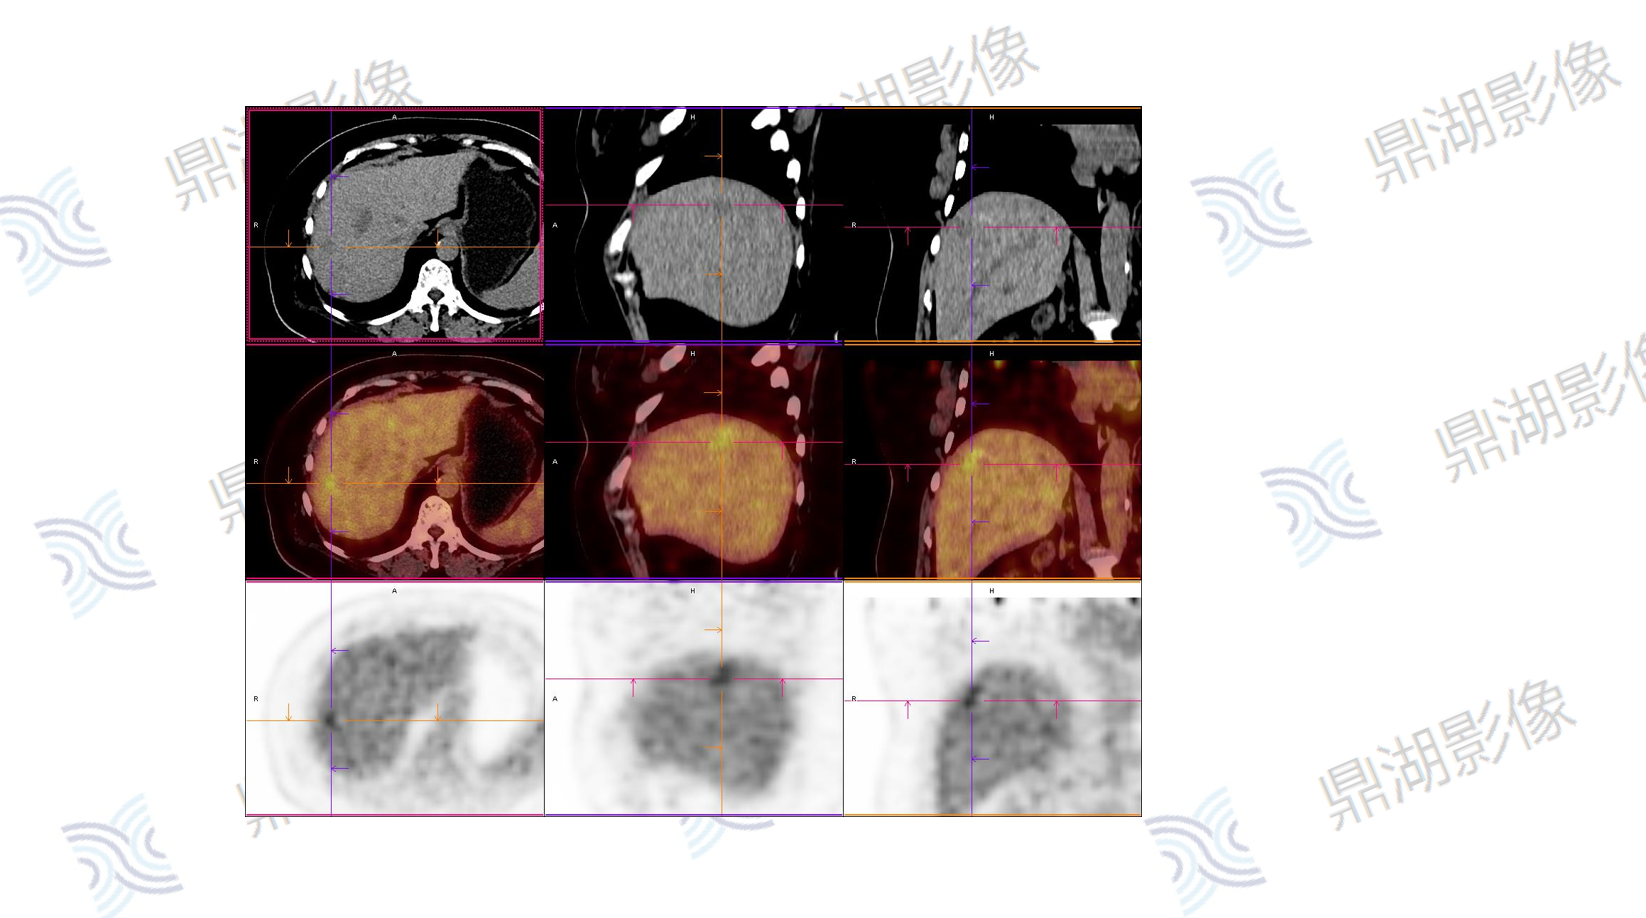

PET

主诉:B超肝实质回声细密增强,MRI提示肝左外叶结节,考虑恶性可能